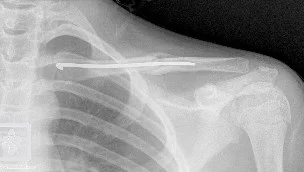

Clavicle Fracture: Management

- Surgical Treatment

- ORIF by Plate and Screws (standard)

- Elastic nail ?